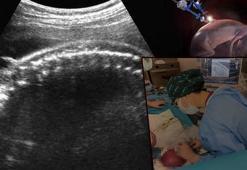

Ankara’da tıp tarihine geçen ameliyat! Anne karnında bebeğin omuriliği başarıyla onarıldı

Ankara’da tıp tarihine geçen ameliyat! Anne karnında bebeğin omuriliği başarıyla onarıldıAnkara Bilkent Şehir Hastanesi’nde 24 haftalık bir bebeğin omuriliğindeki açıklık, rahim içine girilerek yapılan ameliyatla kapatıldı. Dünyada sayılı merkezde gerçekleştirilen bu operasyon, Ankara’da ilk kez başarıyla uygulandı.

Her şey ultrasonla başladı! Anne karnında kurtuluş: Bu bebekler 2 kez doğuyor

Her şey ultrasonla başladı! Anne karnında kurtuluş: Bu bebekler 2 kez doğuyorHamileliği sorunsuz ilerliyordu, ta ki bir ultrasonla hiç beklemediği o haberi alana kadar. Önünde iki seçenek vardı: Ya gebelik sonlandırılacak ya da bebek doğduktan sonra ağır ameliyatlarla mücadele edecekti. Ancak yolu tam da o sırada Prof. Dr. Esra Esim Büyükbayrak ile kesişti. Hem anne hem de bebek, aynı anda ameliyat edilerek hayata işte böyle tutundu.